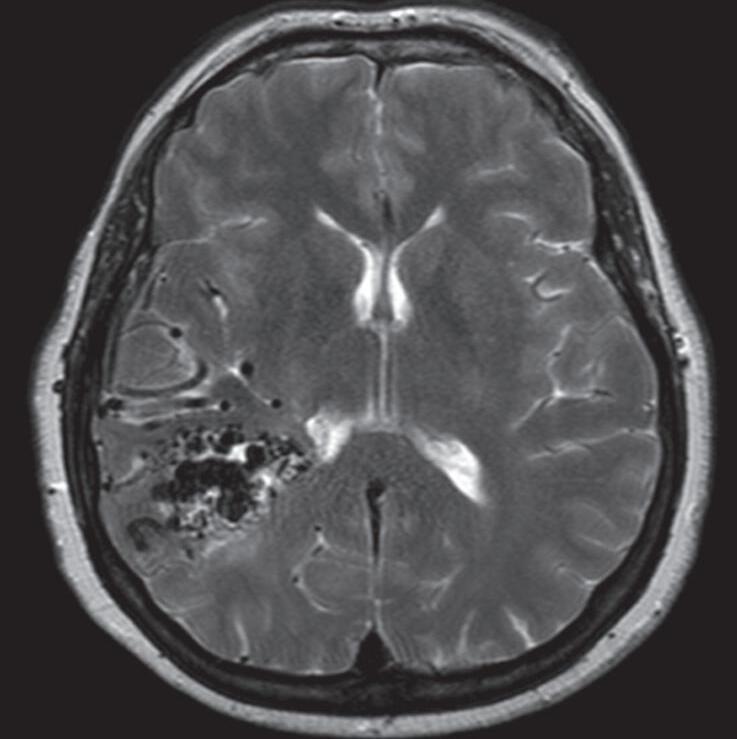

Na anatomia vascular cerebral normal, os capilares são vasos sanguíneos finos e permeáveis, que permitem a troca de nutrientes e resíduos entre o sangue e as células cerebrais, representados pela Figura 1-3. Nas MAVs, a ausência destes capilares promove um arranjo disfuncional dos vasos cerebrais (representado pelas Figuras 1-2 e 1-4) resultando em um fluxo sanguíneo local alterado, aumento da pressão venosa e turbilhonamento do fluxo sanguíneo intranidal. Estes fatores em conjunto, contribuem para o enfraquecimento do endotélio dos vasos envolvidos, elevando assim o risco de ruptura vascular e de sangramento intracraniano.6-8

Fig. 1-8. (a-c) RNM T1 com contraste, cortes sagital (a), coronal (b) e axial (c) demonstrando MAV não rota com nidus localizado no lobo occipital à esquerda (setas longas). (d) Arteriografia digital cerebral com injeção de contraste via carótida direita (AP) mostrando a contribuição da carótida direita na irrigação da MAV contralateral. (e,f) Com injeção de contraste via carótida esquerda, em Perfil e AP respectivamente, observa-se nidus compacto nutrido por ramos da artéria cerebral média à esquerda e a veia de drenagem precoce se dirigindo para o seio sagital superior. Projeções em AP (g) e em perfil (h) demonstrando a contribuição do sistema vertebrobasilar por meio de ramos distais da artéria cerebral posterior à esquerda e drenagem para os seios sagital superior e sigmoide à esquerda (setas curtas).